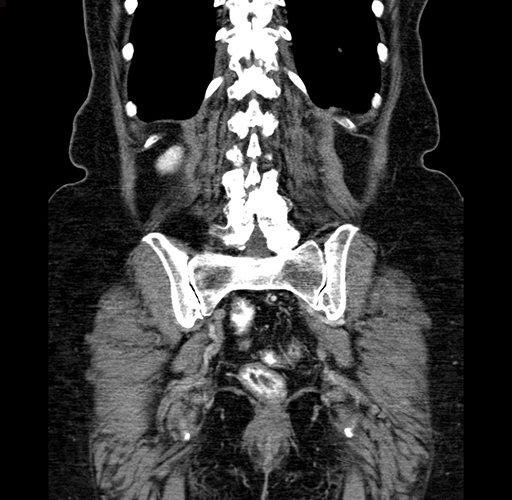

Coronal Venous